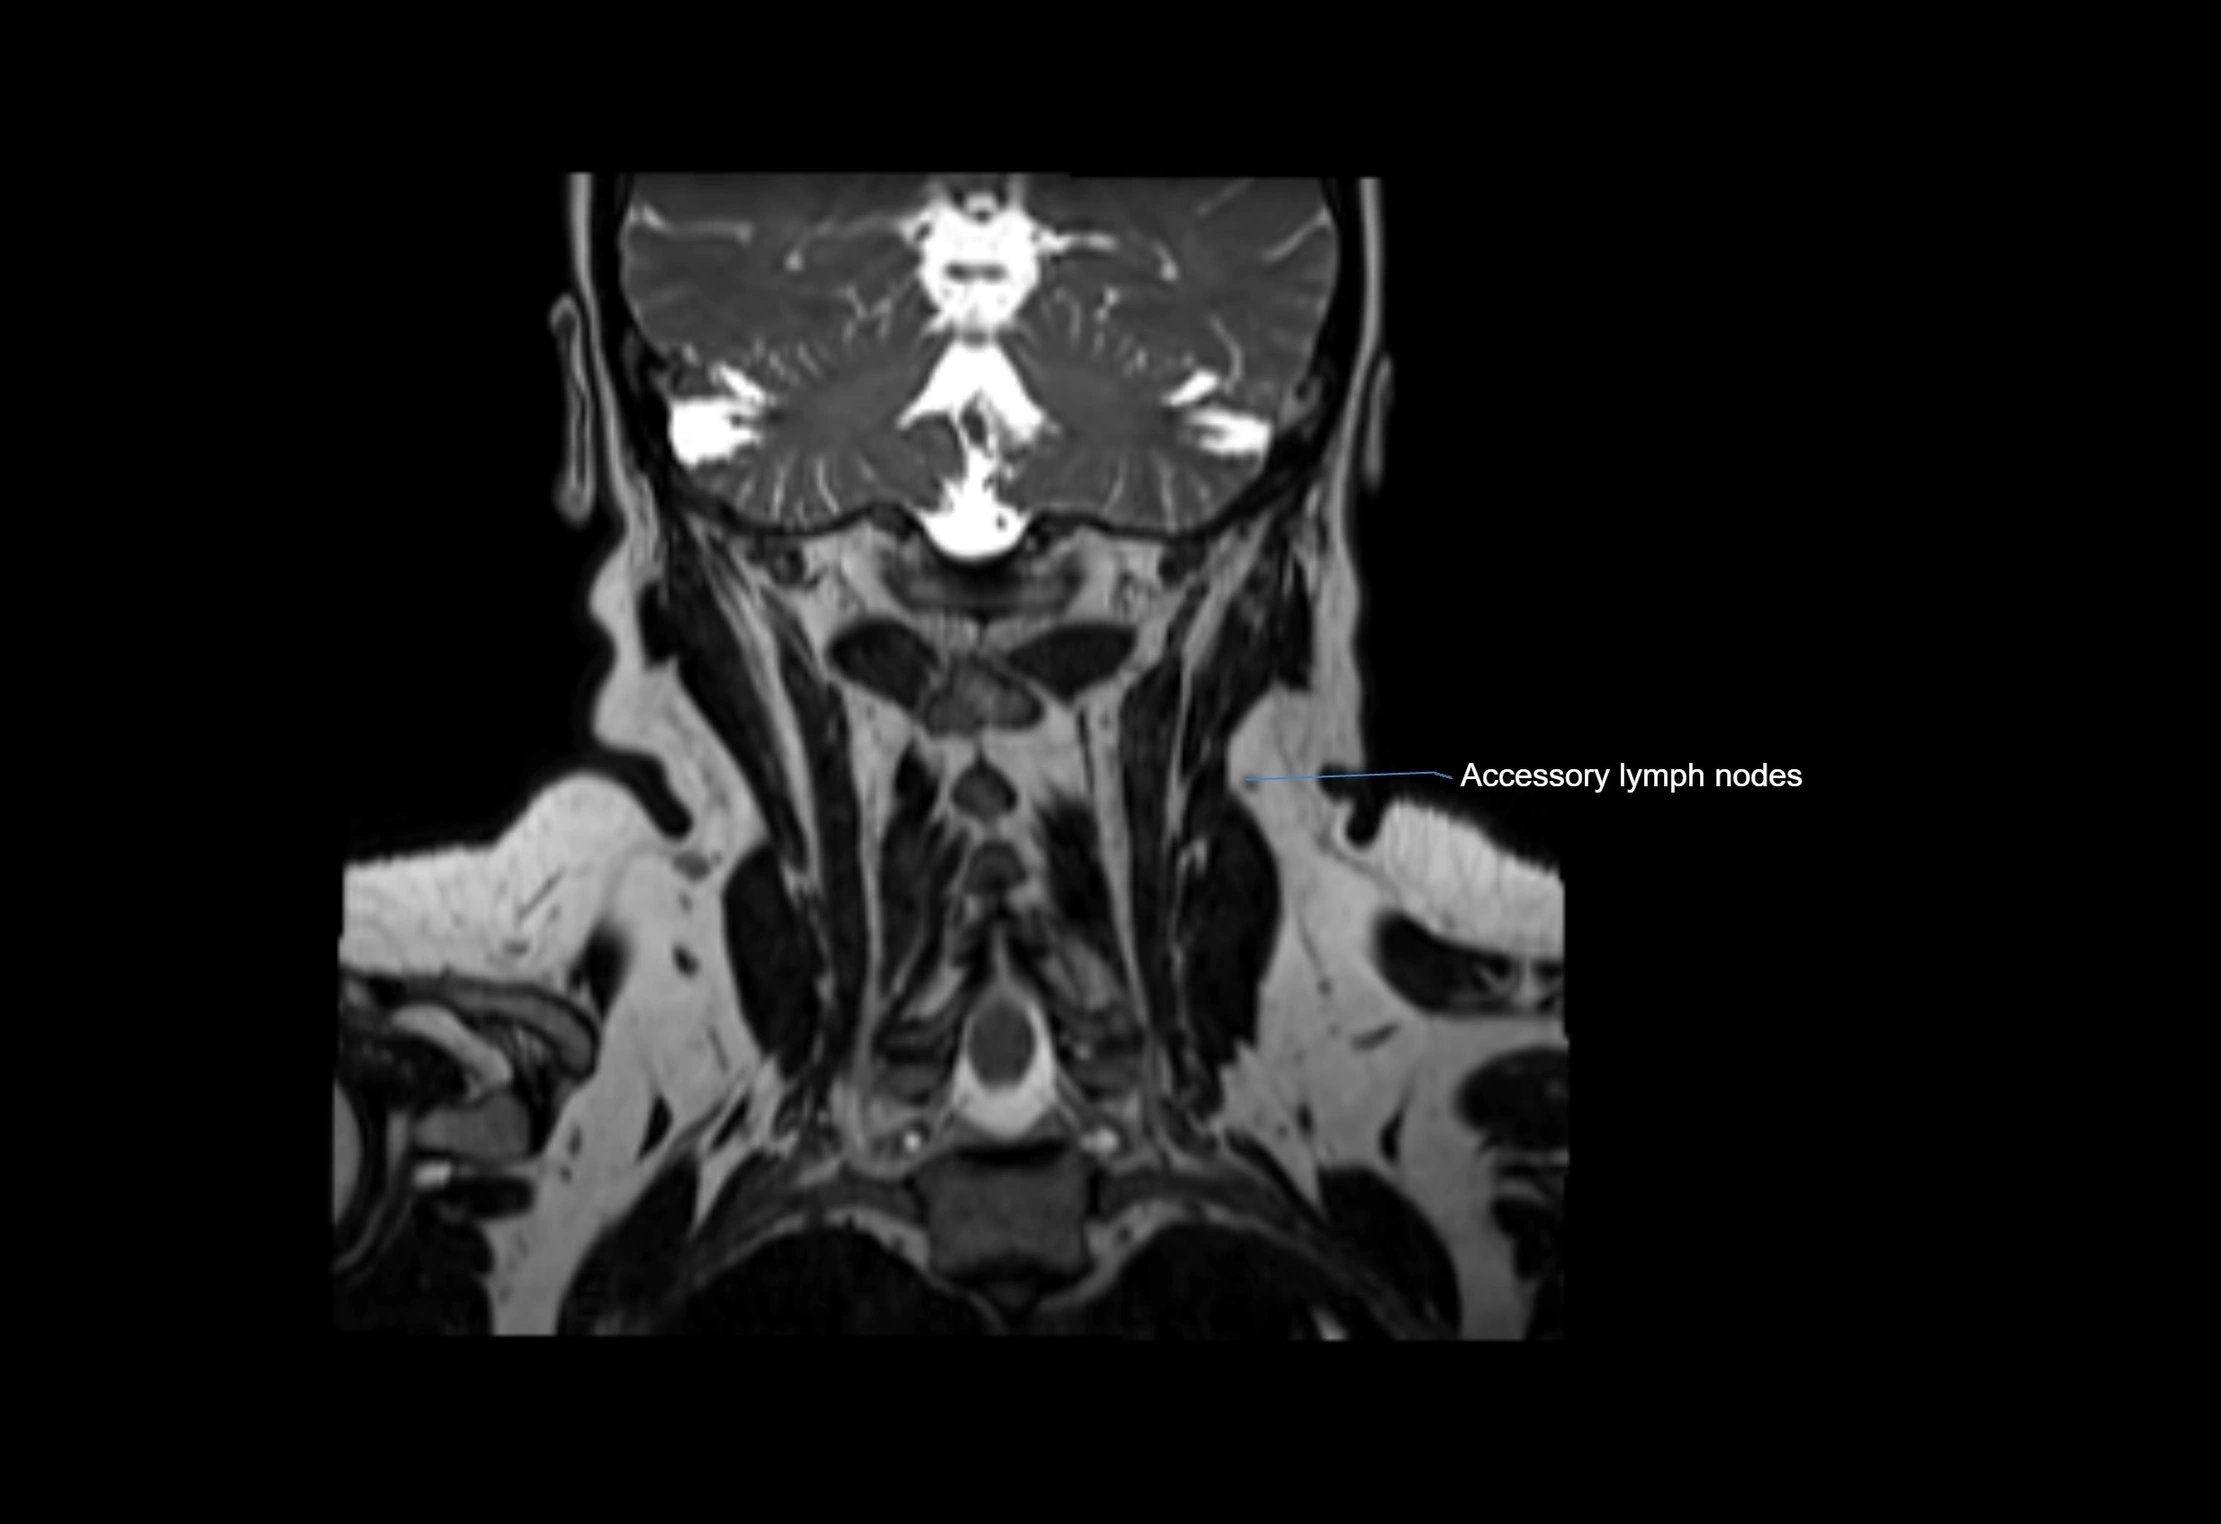

Accessory lymph nodes

Accessory lymph nodes are small, secondary lymph nodes located along the main facial and cervical lymphatic chains, often adjacent to primary lymph nodes, such as preauricular, submandibular, or occipital nodes. They are typically less than 5 mm in diameter, embedded within subcutaneous fat or connective tissue, and may be variable in number and location. These nodes provide additional filtration and immune surveillance for lymph collected from the face, scalp, and neck regions. Accessory lymph nodes are usually non-palpable in healthy individuals but may enlarge in response to infection, inflammation, or metastasis, making them clinically significant.

MRI Appearance

T1-weighted images:

• Normal accessory nodes appear as small, oval hypointense to intermediate signal structures within subcutaneous fat

• Surrounded by hyperintense fat, enhancing contrast for visualization

• Pathological nodes may appear enlarged or rounded, sometimes with cortical thickening

T2-weighted images:

• Nodes show intermediate signal, with surrounding fat bright

• Useful for detecting edema, inflammation, or infiltration

• Fatty hilum may appear slightly hyperintense relative to cortex

MRI images

image